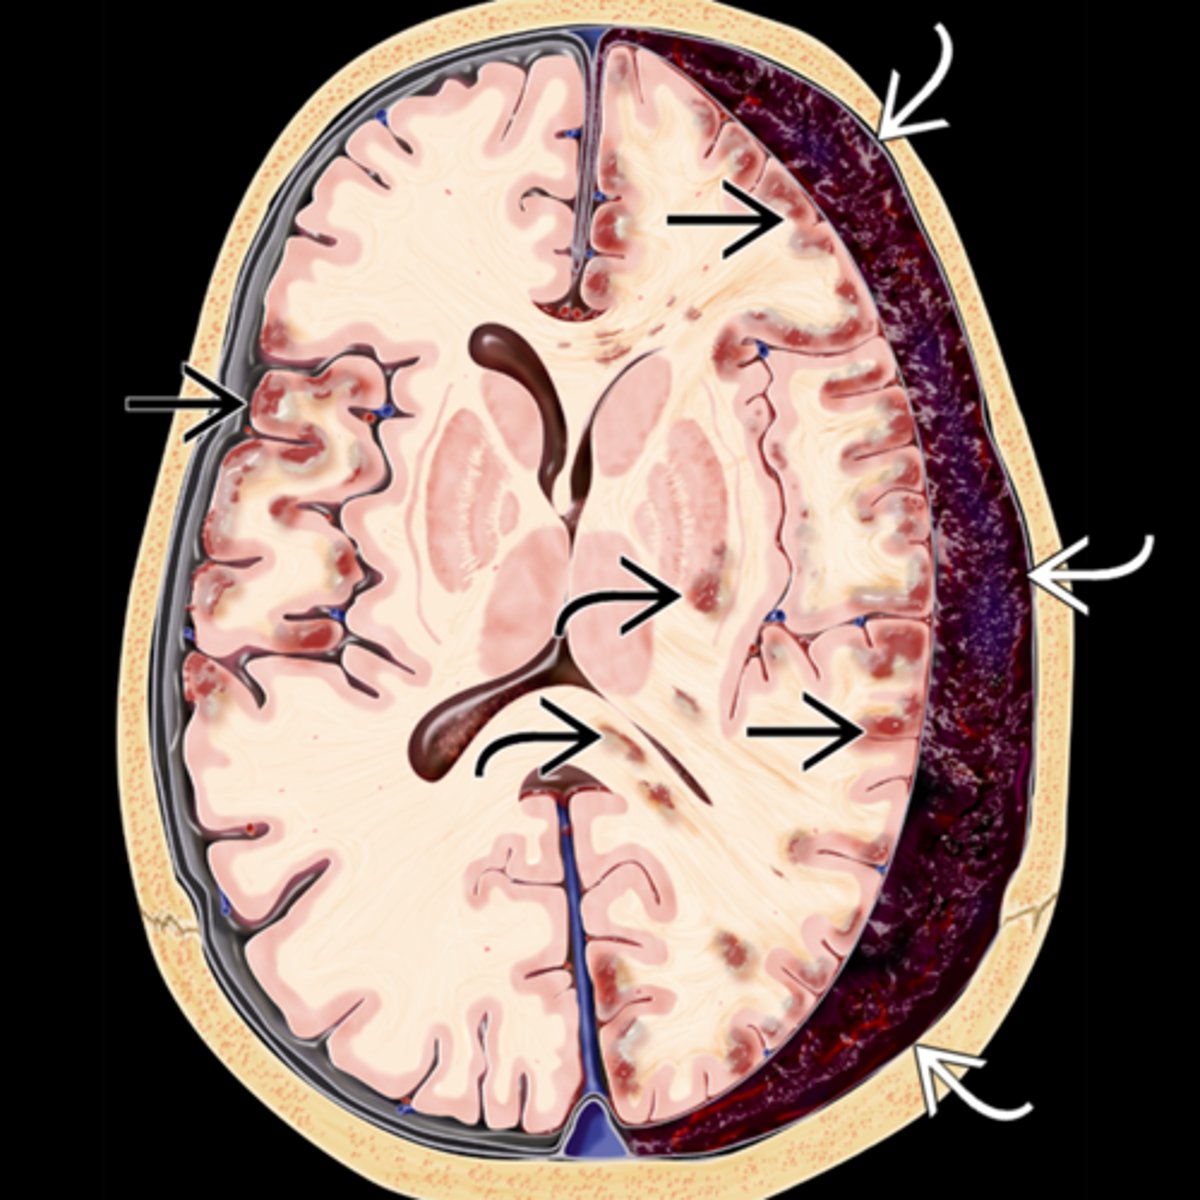

What is Uncal syndrome?

fast expanding mass, hemorrhage, tumor = increased ICP = brainstem compression and herniation down into foramen magnum (fatal!) = fixed, dilated pupil

What do we call the fixed, dilated pupil seen in Uncal syndrome?

Hutchinson pupil

Explain the progression of the Hutchinson pupil seen in Uncal syndrome.

1. miotic pupil due to initial cerbreal edema

2. ipsilateral dilated pupil due to expanding mass on that side

3. bilateral fixed and dilated pupils eventually

What are 3 other ocular signs of Uncal syndrome?

bilateral papilledema bc of increased ICP (bilateral even if only 1 pupil involved)

homonymous hemianopsia bc posterior cerebral arteries are occluded by mass = calcarine cortex ischemia

EOM paralysis = diplopia but mostly very late in the disease

What is the most common cause of Uncal syndrome?

chronic subdural hematoma from head trauma esp in inebriated pt's

What are some less common causes of Uncal syndrome?

extradural hematoma from injury

subdural hematoma from drugs

Explain the series of a events that causes a subdural hematoma, Uncal syndrome, and eventually death.

trauma = brain moves ant to post = cerebral veins in subdural space rip = blood fills subdural space = fibrous dura and arachnoid mesothelium beneath create a sac around the cot = sac breaks = blood enters brain = pt is sick and dies

Where is the Uncal region, affected in Uncal syndrome?

uncas of parahippocampal gyrus (inferior area of temporal lobe) = lateral to the brainstem = lateral to CN III in brainstem

Explain how the Uncal region can affect CN III in Uncal syndrome.

CN III leaves brainstem = pupillomotor fibers move dorsomedially = uncus herniates = compresses CN III dorsomedially against petroclinoid ligament and dorsum sellae = pupil is blown